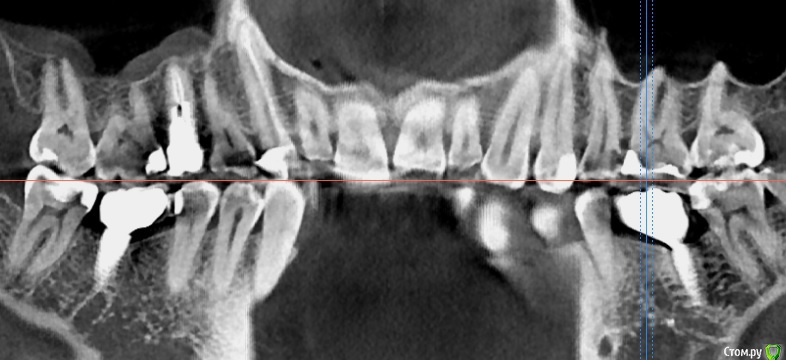

vad Опубликовано 17 октября, 2019 Поделиться Опубликовано 17 октября, 2019 Импланты металлокерамика установлены 1.5-2 года назад.Между ними и соседними зубами попадает пища, очень много пищи, особенно проблемный зуб слева.В клинике говорят, что нужно менять имплант на циркониевый, естественно за деньги, так как гарантия кончилась. Ссылка на комментарий

AndyAndy Опубликовано 17 октября, 2019 Поделиться Опубликовано 17 октября, 2019 Пища попадает сверху между коронкой и зубами или сбоку? Проверьте зубной нитью, проваливается она или есть сопротивление. Если дело в слабом контакте, этот вопрос решается заменой/коррекцией коронки, пока не вижу причин менять непосредственно имплантат. Фото во рту можете сделать? Ссылка на комментарий

vad Опубликовано 17 октября, 2019 Автор Поделиться Опубликовано 17 октября, 2019 (изменено) "коронки", конечно.Нити оказывается сопротивление, меньше чем между другими зубами (там еле лезет).Пища попадает спереди и сзади в щель между зубами, и между ними влазит деревянная зубная палочка. Изменено 17 октября, 2019 пользователем vad Ссылка на комментарий

Pavel-Pskov Опубликовано 18 октября, 2019 Поделиться Опубликовано 18 октября, 2019 Для начала проконсультироваться у грамотного терапевта стоматолога, он скажет поможет или нет замена пломб, по понораме мы все только предполагаем, что может помочь. Ссылка на комментарий

red_butler Опубликовано 18 октября, 2019 Поделиться Опубликовано 18 октября, 2019 Покажите фото во рту и обычный панорамный снимок Ссылка на комментарий

vad Опубликовано 18 октября, 2019 Автор Поделиться Опубликовано 18 октября, 2019 (изменено) обычный панорамный снимок У меня только КТ. Могу покрутить в любой проекции и с любой глубиной, в первом сообщении 1 мм. Изменено 18 октября, 2019 пользователем vad Ссылка на комментарий